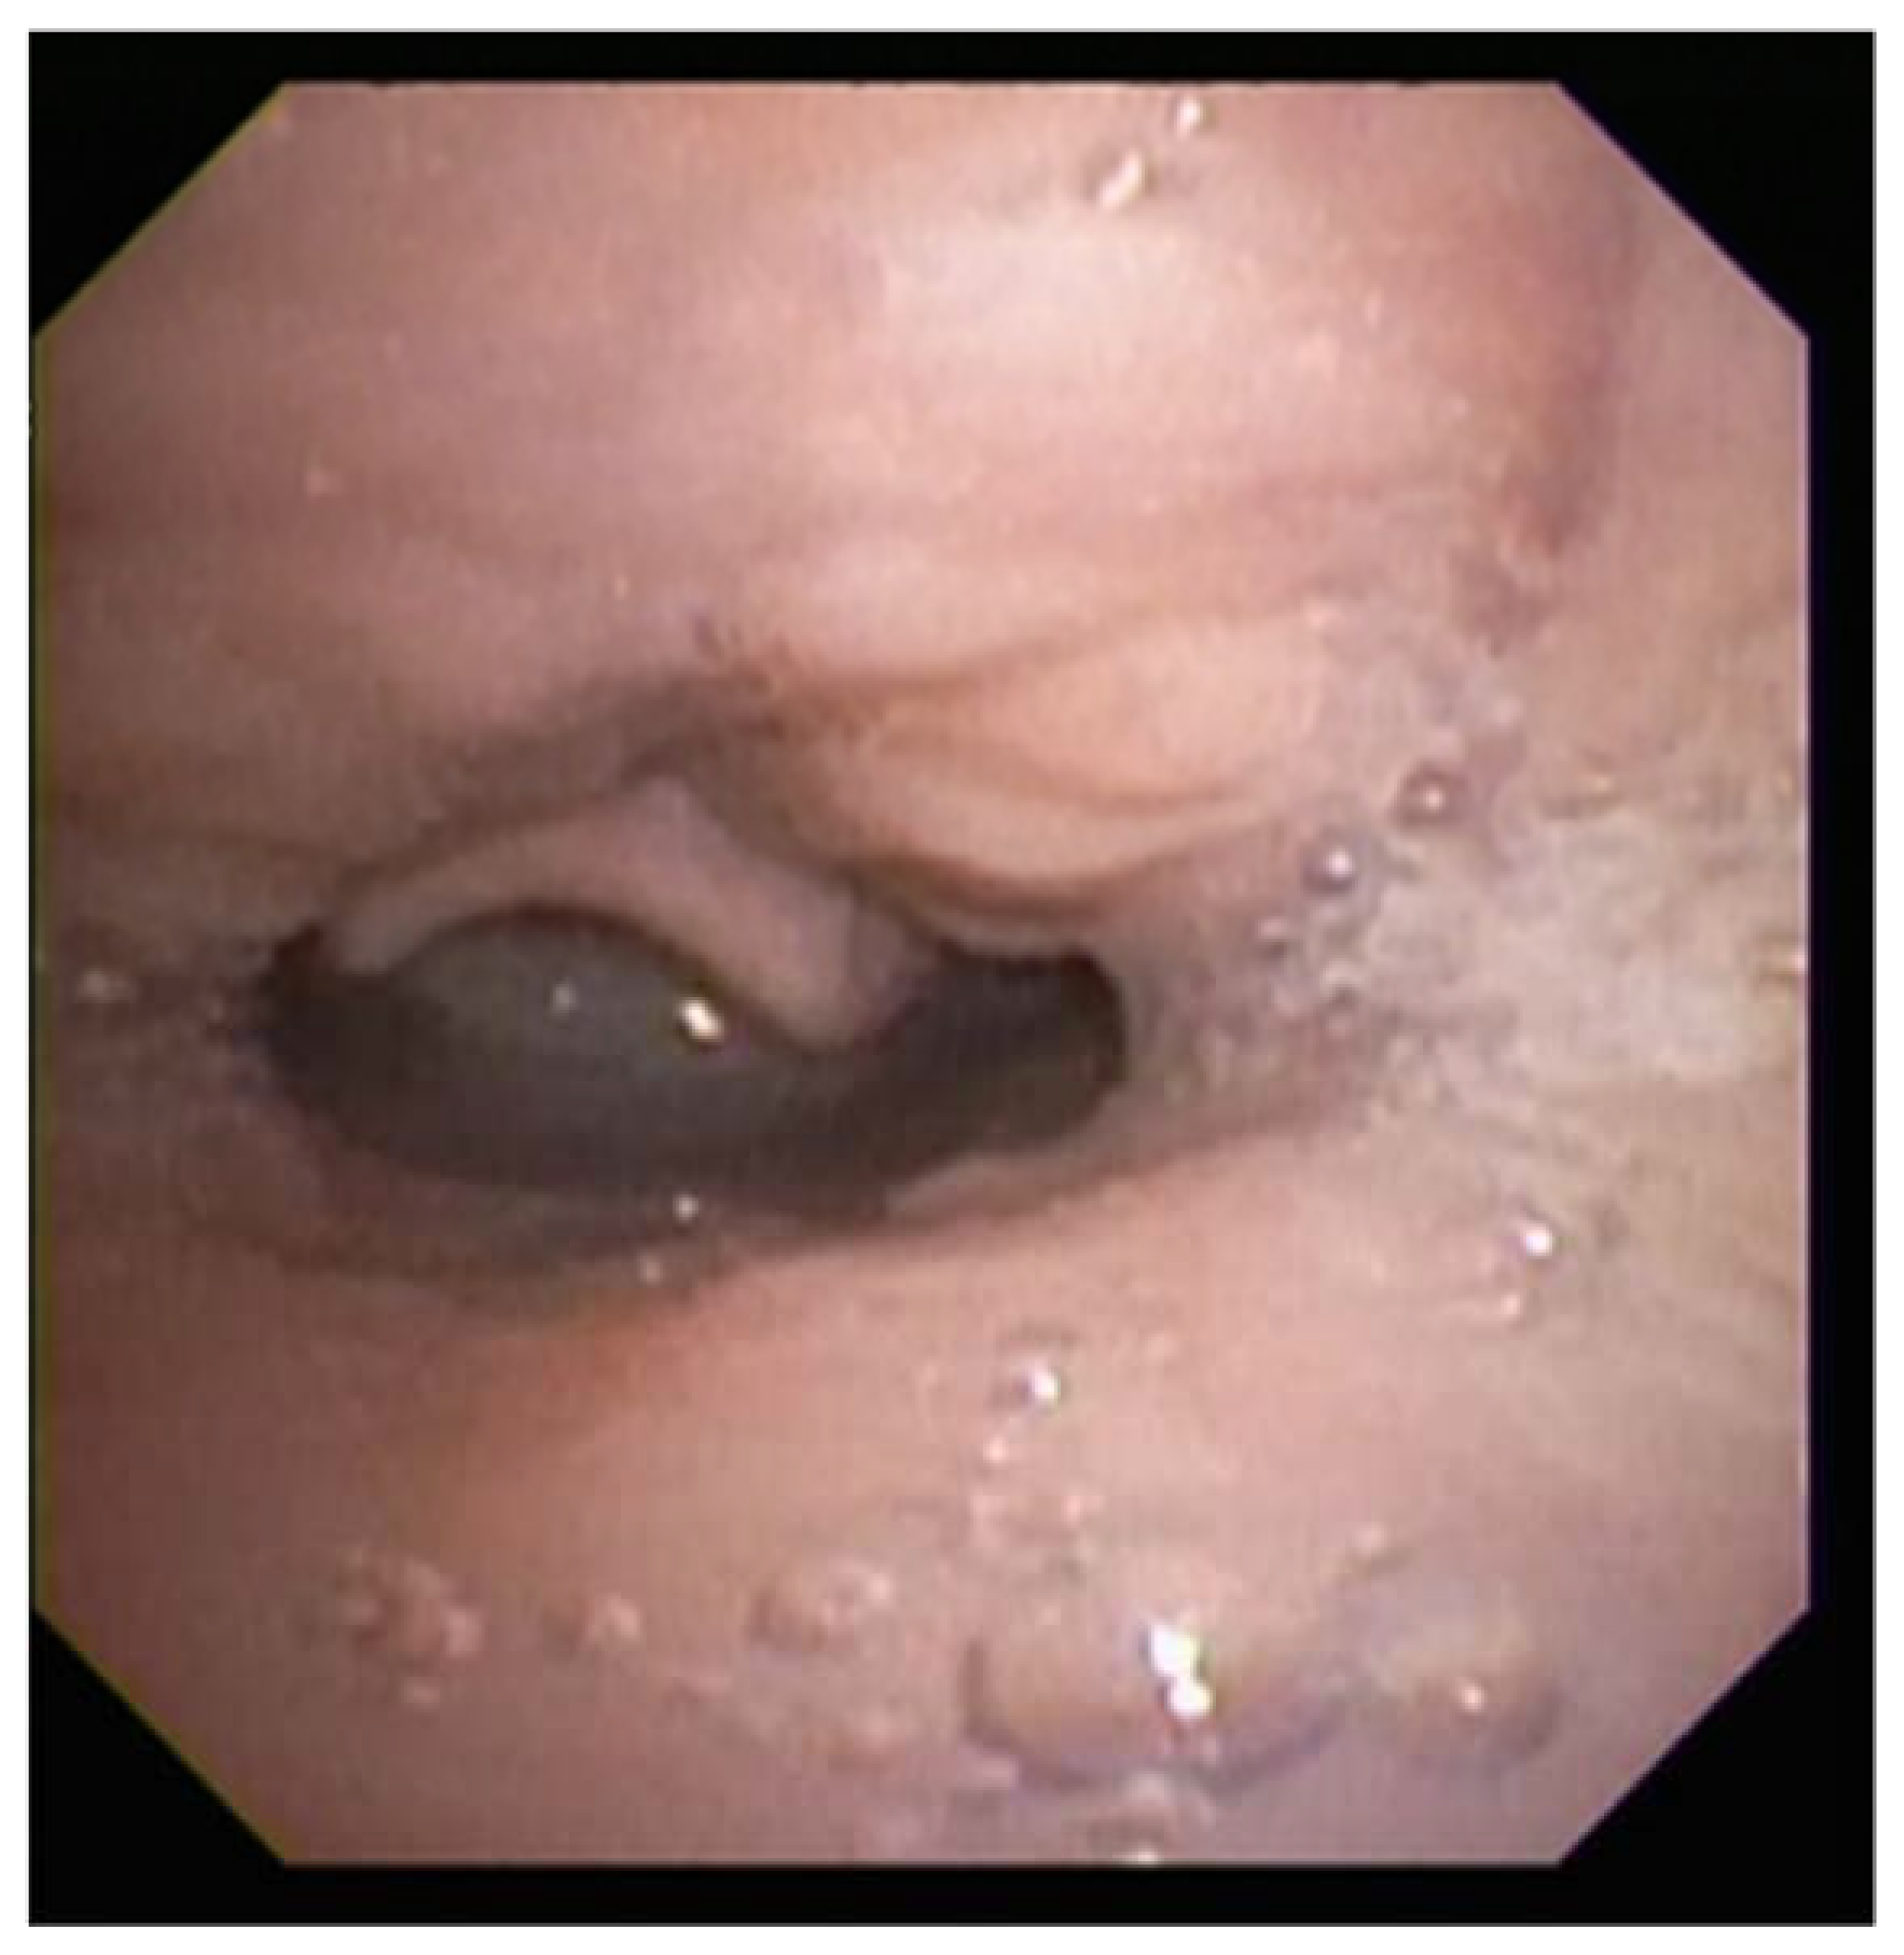

2.11. Congenital Neck Masses

- Li, Y.; Irace, A.L.; Dombrowski, N.D.; Perez-Atayde, A.R.; Robson, C.D.; Rahbar, R. Vallecular cyst in the pediatric population: Evaluation and management. Int. J. Pediatr. Otorhinolaryngol. 2018, 113, 198–203. [Google Scholar] [CrossRef]

- Suzuki, J.; Hashimoto, S.; Watanabe, K.; Takahashi, K. Congenital vallecular cyst in an infant: Case report and review of 52 recent cases. J. Laryngol. Otol. 2011, 125, 1199–1203. [Google Scholar] [CrossRef] [PubMed]

- Breysem, L.; Goosens, V.; Vander Poorten, V.; Vanhole, C.; Proesmans, M.; Smet, M. Vallecular cyst as a cause of congenital stridor: Report of five patients. Pediatr. Radiol. 2009, 39, 828–831. [Google Scholar] [CrossRef] [PubMed]

- Hsieh, L.C.; Yang, C.C.; Su, C.H.; Lee, K.S.; Chen, B.N.; Wang, L.T. The outcomes of infantile vallecular cyst post CO2 laser treatment. Int. J. Pediatr. Otorhinolaryngol. 2013, 77, 655–657. [Google Scholar] [CrossRef]